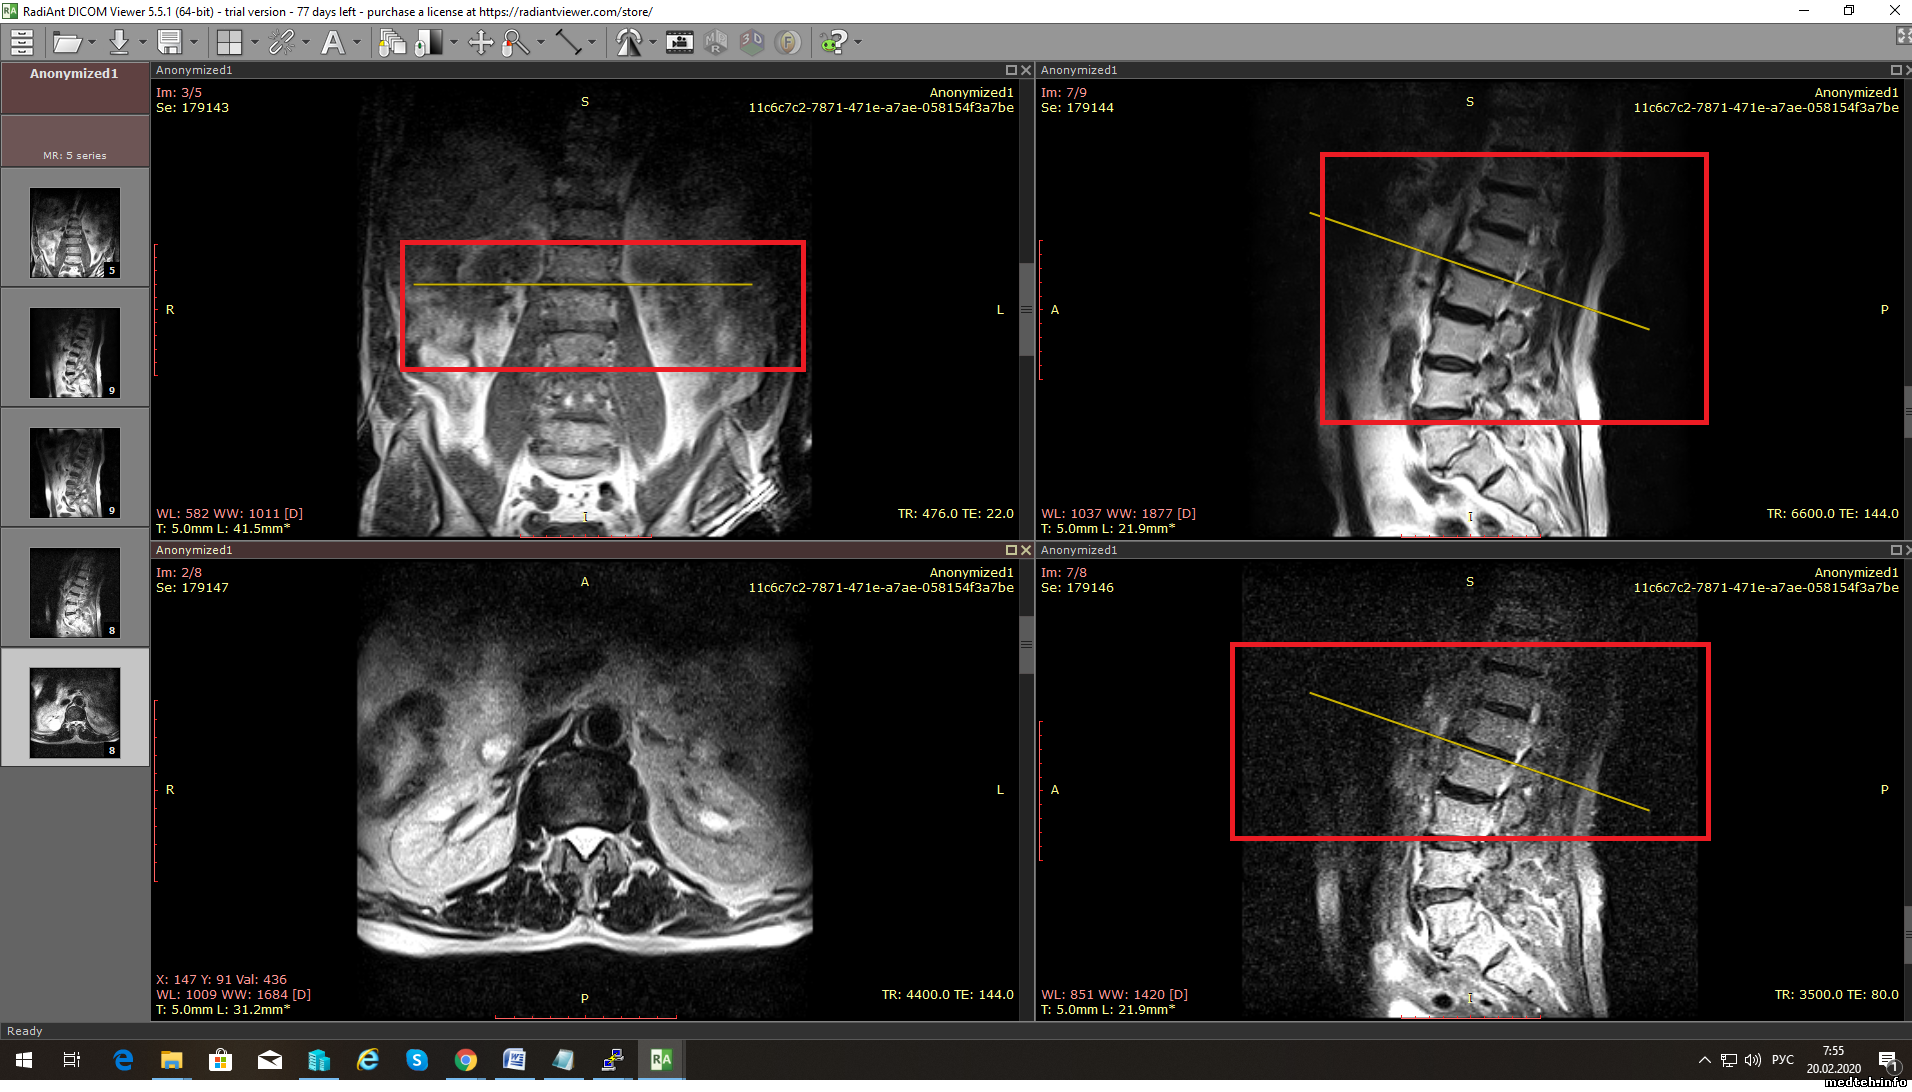

Всем доброго времени суток!

Подскажите, пожалуйста, почему могут не работать контрольные линии (reference line) в eFilm (версии 3.1 и 4.1), смотрел теги в DICOM Dump - теги и инфа в них присутствует.

Скачал RadiAnt, линии отображаются. загрузил снимки в Orthanc, тоже отображаются ...

Efilm не отображает текущее положение среза не показывает в другом окне. Кто нибудь лечил такое ?

RadiAnt - отображает.

1451320.png (961.6 Kb)